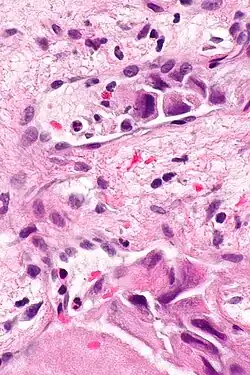

Lymphovascular invasion (LVI or lymphovascular space invasion) is the invasion of a cancer to the blood vessels and/or lymphatics.

Lymphovascular invasion, especially in carcinomas, usually precedes spread to the lymph nodes that drain the tissue in which the tumour arose. Conversely, cancers with lymph node spread (known as a lymph node metastases), usually have lymphovascular invasion. Lymph node metastases usually precede secondary tumours, i.e. distant metastases.

The absence of LVI in the context of proven lymph node metastasis is usually thought to be due to sampling error.[1]